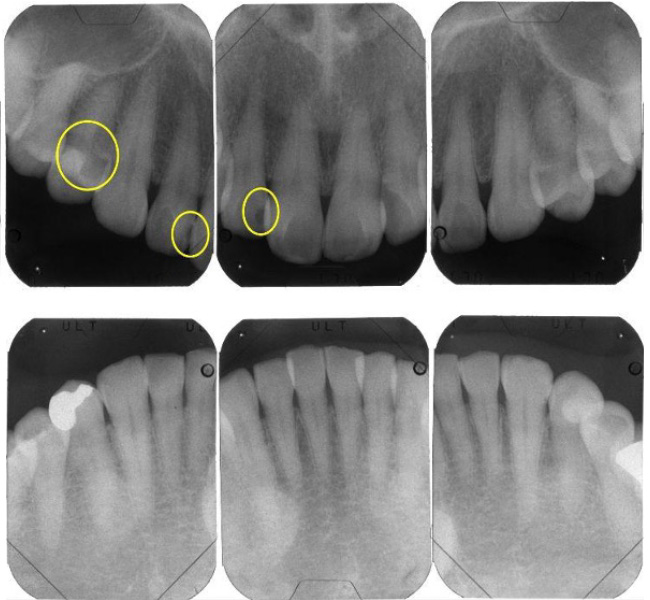

治療前

(レントゲン)

【レントゲン】左下奥歯のレントゲン所見

一番奥の歯(左下7番)は、被せ物の下の土台にヒビ(破折)が入っており、歯の内部と外部の両方から細菌感染が進んでいる「末期的な状態」です。周囲の骨が広範囲に溶け、大きな黒い影として写っています。

その手前の歯(左下6番)は、過去に根を分割する処置がされていますが、土台が根の方向からズレており、噛み合わせの強い力に耐えきれず地盤(骨)を半分以上失っています。

どちらの歯も、これ以上の補修では建物の重み(噛み合わせの力)を支えられず、放置すれば周囲の健康な骨までさらに溶かしてしまうため、将来を見据えて「戦略的な抜歯」を選択しました。